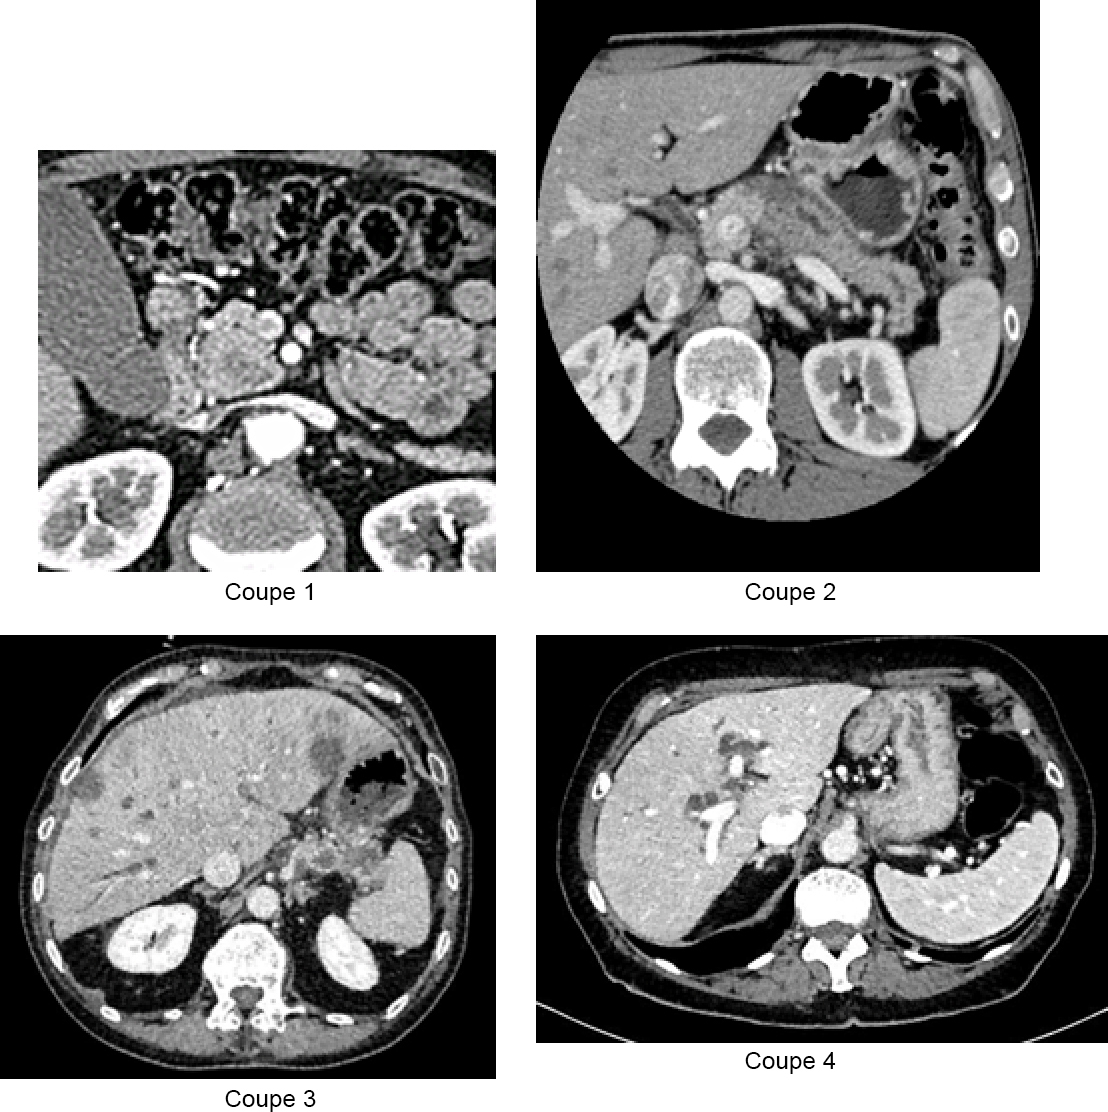

Vous recevez les résultats du bilan biologique : – hémoglobine (Hb) = 10,1 g/dL ; volume globulaire moyen (VGM) = 75 fl ; plaquettes = 550 G/L ; leucocytes = 18 G/L dont polynucléaires neutrophiles (PNN) à 15 G/L ; – natrémie = 136 mmol/L ; kaliémie = 3,4 mmol/L ; créatininémie = 70 umol/L ; – aspartate aminotransférase (ASAT) = 230 U/L (N < 30) ; alanine aminotransférase (ALAT) = 241 U/L (N < 30) ; gamma GT = 879 U/L (N < 60) ; phosphatases alcalines = 967 U/L (N < 100) ; bilirubine totale = 460 µmol/L (N < 17) ; bilirubine conjuguée = 400 µmol/L ; protéine C réactive (CRP) = 300 mg/L ; ferritine = 974 µg/L ; coefficient de saturation de la transferrine = 21 % ; taux de prothrombine (TP) = 45 %, facteur V = 98 %. Voici les coupes de scanner : Figure 1 (Source : Elisabeth Capelle, La Revue du Praticien)

Les hypodensités hépatiques sont probablement des métastases hépatiques, étant donné leur nombre, leur forme et surtout le contexte.

Figure 2 (Source : Elisabeth Capelle, La Revue du Praticien)

Vous faites donc le diagnostic d’angiocholite sur obstruction des voies biliaires par une tumeur de la tête du pancréas, associée à des images évocatrices de métastases hépatiques.